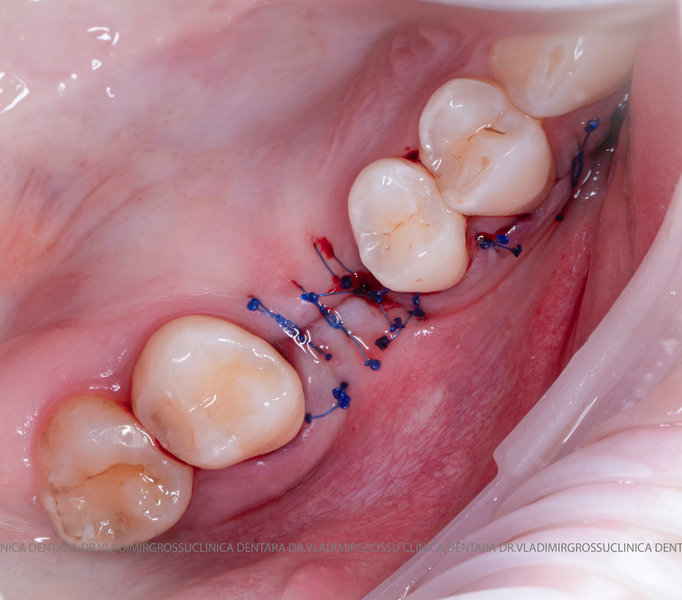

Adiția de gingie (gingivoplastia)

Aditia gingivală este o procedură chirurgicală ce corectează diverse probleme estetice și funcționale, cum ar fi recesiunea gingivală. În implantologia modernă, aditia de țesut moale este utilizată aproape în fiecare intervenție de inserție a implantului dentar pentru a asigura un aspect estetic natural și o bună integrare a implantului în cavitatea bucală.

Adiția osoasă are un rol crucial pentru poziționarea corectă și stabilă a implanturilor dentare. Clinica stomatologică Dr. Grossu din Chișinău promovează o abordare chirurgicală estetică și predictibilă, adaptată fiecărui caz în parte.